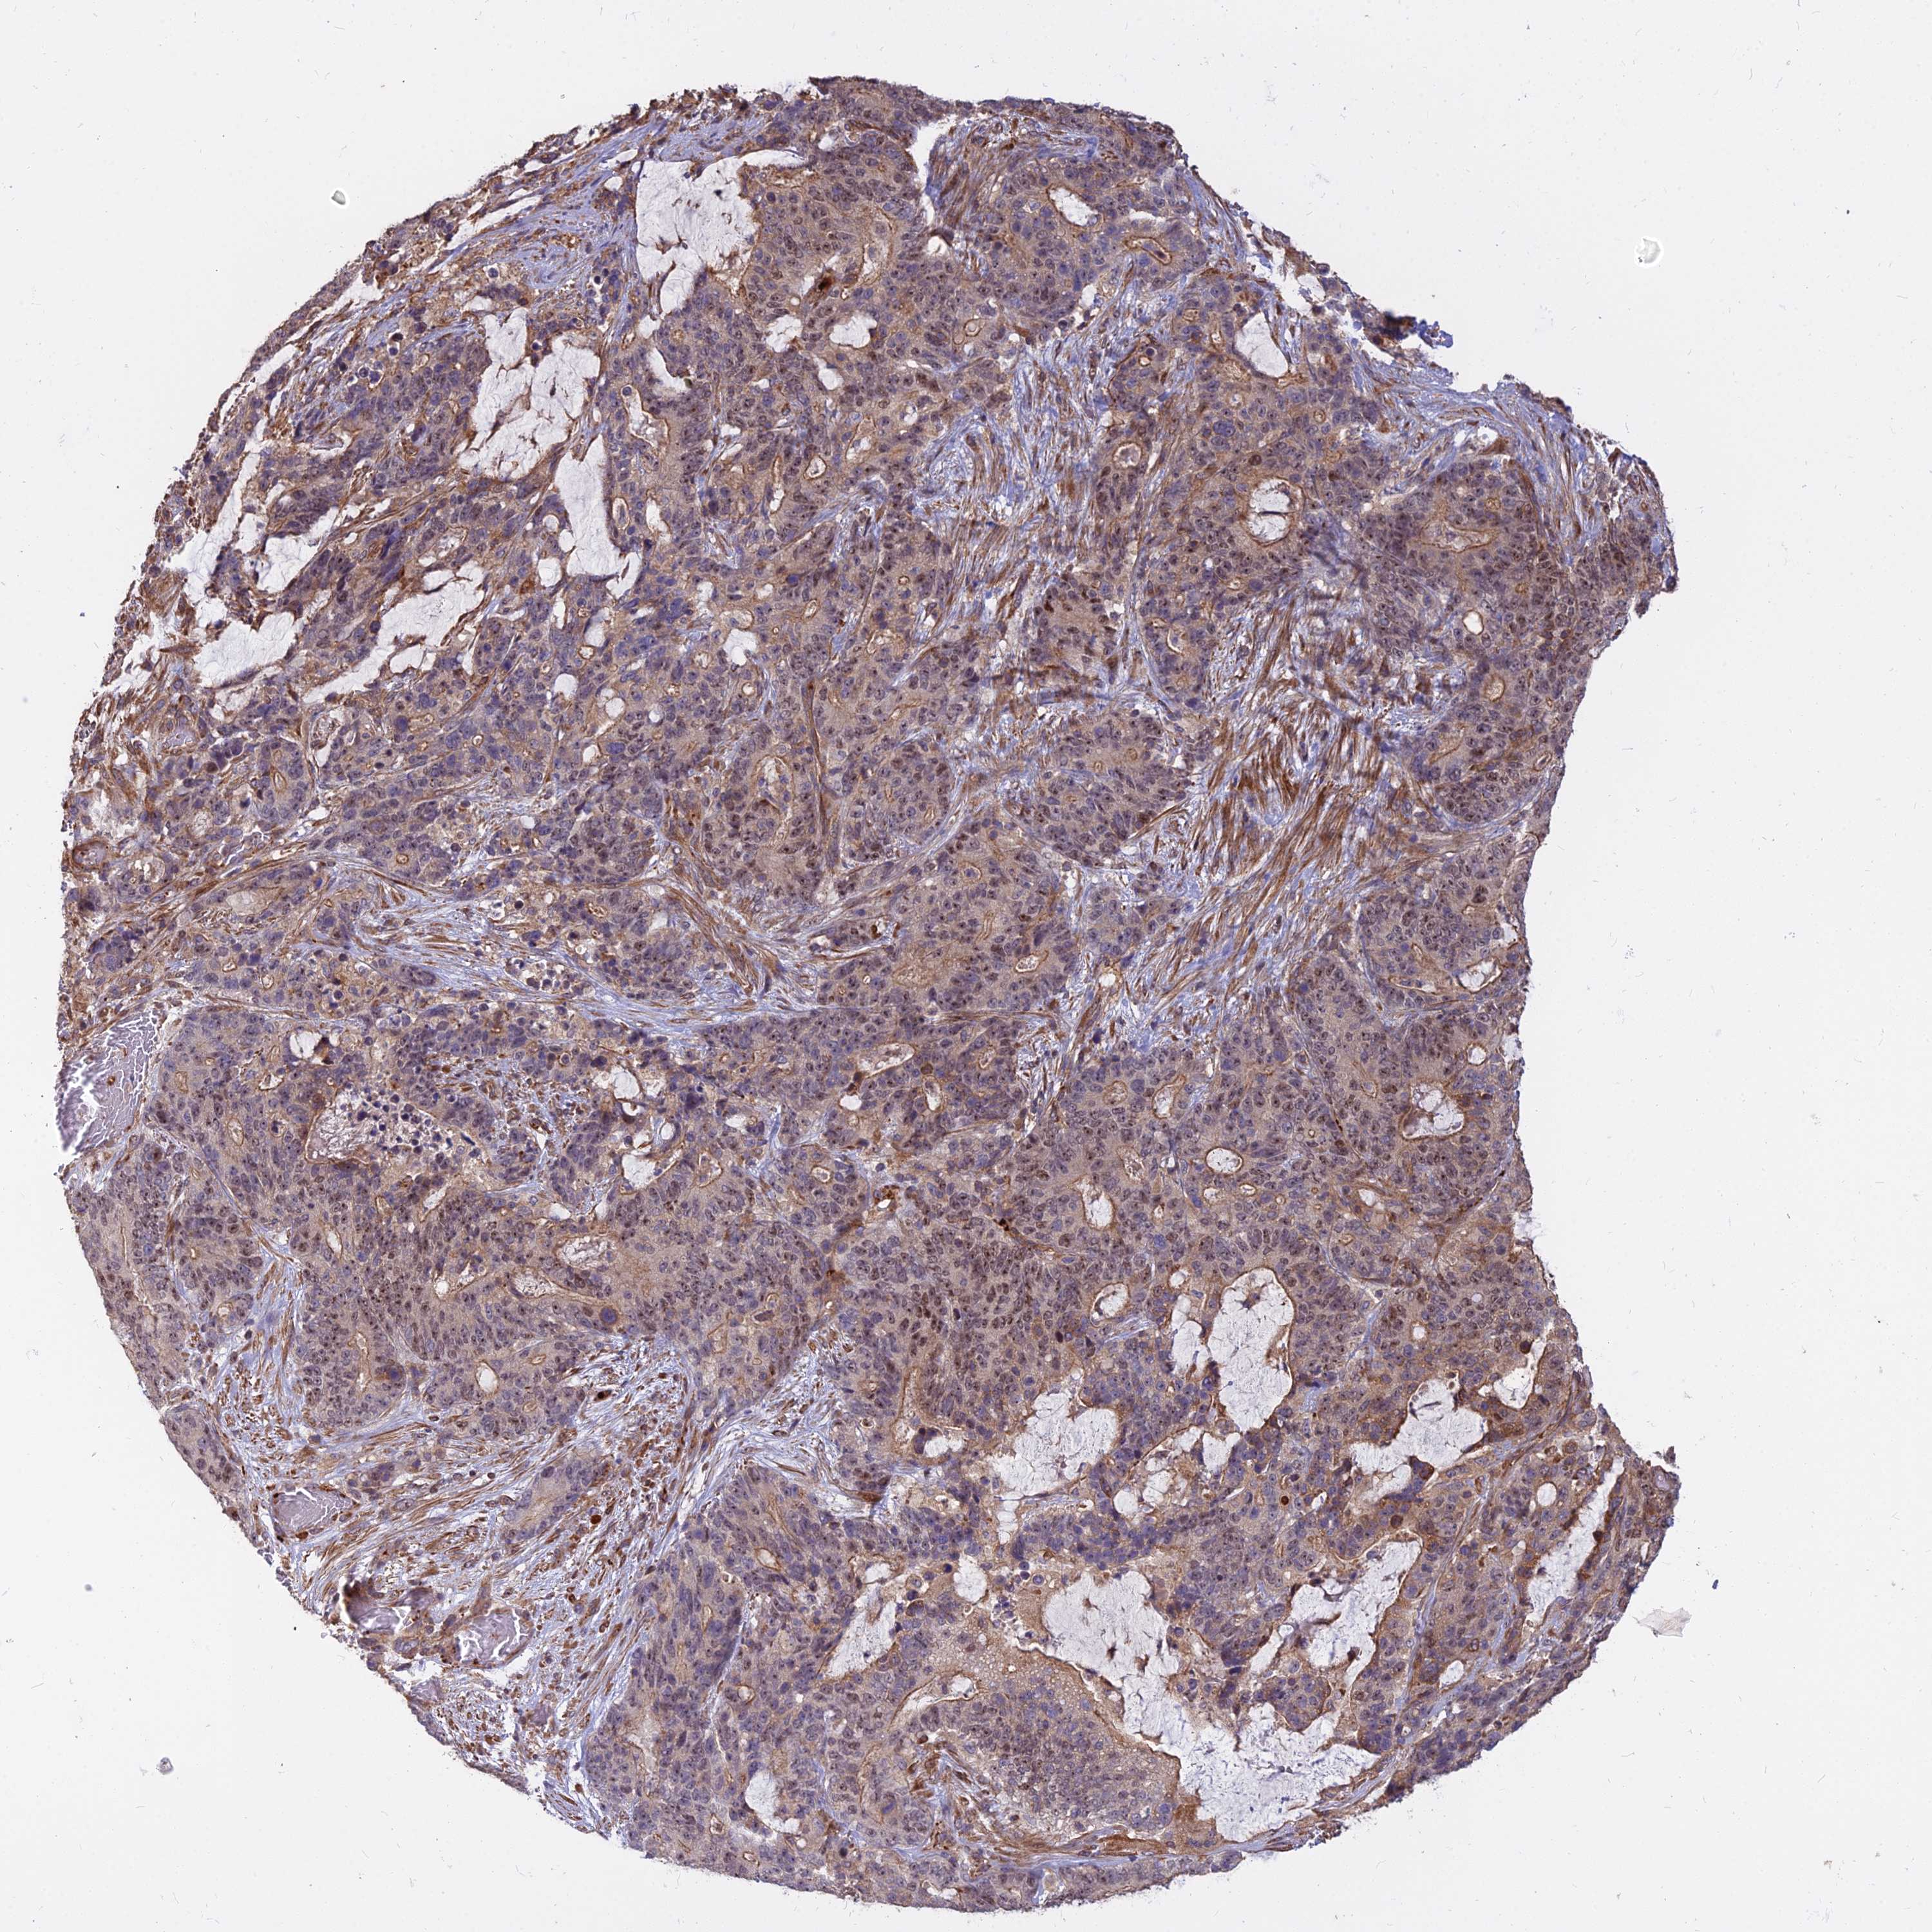

STOMACH CANCER - Protein expressioni

A mouse-over function shows sample information and annotation data. Click on an image to view it in a full screen mode. Samples can be filtered based on level of antibody staining by selecting one or several of the following categories: high, medium, low and not detected. The assay and annotation is described here.

Note that samples used for immunohistochemistry by the Human Protein Atlas do not correspond to samples in the TCGA dataset.

Antibody stainingi

Antibody staining in the annotated cell types in the current human tissue is reported as not detected, low, medium, or high, based on conventional immunohistochemistry profiling in selected tissues. This score is based on the combination of the staining intensity and fraction of stained cells.

Each image is clickable and will lead to virtual microscopy that enables deeper exploration of all samples and also displays staining intensity scores, fraction scores and subcellular localization as well as patient and tissue information for each sample.

Antibody HPA044960

Staining

High

Medium

Low

Not detected

Intensity

Strong

Moderate

Weak

Negative

Quantity

>75%

75%-25%

<25%

None

Location

Nuclear

Cytoplasmic/membranous

Cytoplasmic/membranous,nuclear

Adenocarcinoma, NOS